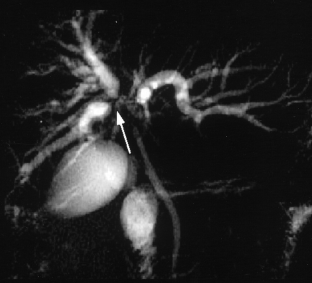

Usual and unusual causes of extrahepatic cholestasis: assessment with magnetic resonance cholangiography and fast MRI

Cholestasis may result from hepatocellular (intrahepatic) disease or biliary tract (extrahepatic) abnormalities. Etiologies causing extrahepatic cholestasis are extremely diverse and invasive procedures, such as endoscopic retrograde cholangiopancreatography (ERCP) and percutaneous transhepatic cholangiography (PTC), were previously required to establish the diagnosis. Due to refinements of magnetic resonance imaging (MRI) techniques, the patient with extrahepatic cholestasis currently can be evaluated noninvasively, and the information revealed frequently exceeds the findings obtained by ERCP and PTC. In this essay, we illustrate the classic MR cholangiographic (MRC) and MRI features of a variety of disorders causing extrahepatic cholestasis, including non-neoplastic disorders of the biliary tract (congenital abnormalities, infectious processes, iatrogenic disorders, and postsurgical complications) and neoplastic conditions (e.g., tumors of the pancreas, biliary tree, liver, ampulla, and regional lymph nodes). In most cases, familiarity with the key MRC features in addition to information obtained via cross-sectional MR images provide sufficient information for adequate lesion characterization.